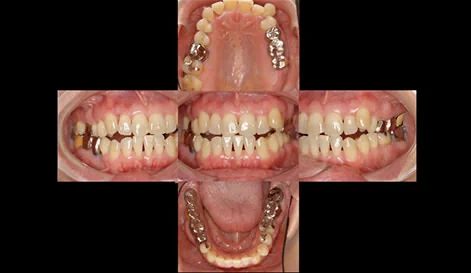

新しく入れる奥歯に過度な負担がかからないようにするために、前歯のかみ合わせを裏側からの見えない矯正で治療します。

歯ならびとかみ合わせを整えたら、CTスキャンで設計したインプラントを、正確な位置に埋入します。

かみ合わせが悪いままインプラントを入れても、また以前と同じように問題が再発してしまいます。

最後にセラミックスを被せて終了です。

しっかり噛めて、歯が長持ちする環境が整いました。